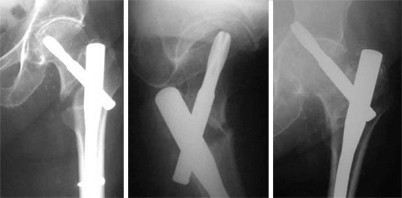

Die intramedullaere stabilisierung von per und subtrochantaeren femurfrakturen ist der der goldstandard.

The pfna has a medial lateral angle of 60 this allows insertion at the tip of the greater. Cases performed with the pfn and pfna. Gamma3 long nail is intended for fixation of stable and unstable femoral fractures occurring from the base of the femoral neck extending distally to a point approximately 10cm proximal to the intracondylar notch including fractures of the basilar neck intertrochanteric fractures peritrochanteric fractures subtrochanteric fractures and femoral shaft fractures.

Pfna nagel optimaler sitz das anatomisch vorgeformte design gewaehrleistet eine optimale pass genauigkeit im femur das design der femurnaegel pfn und pfna hat sich in ueber 450000 implantationen klinisch bewaehrt.